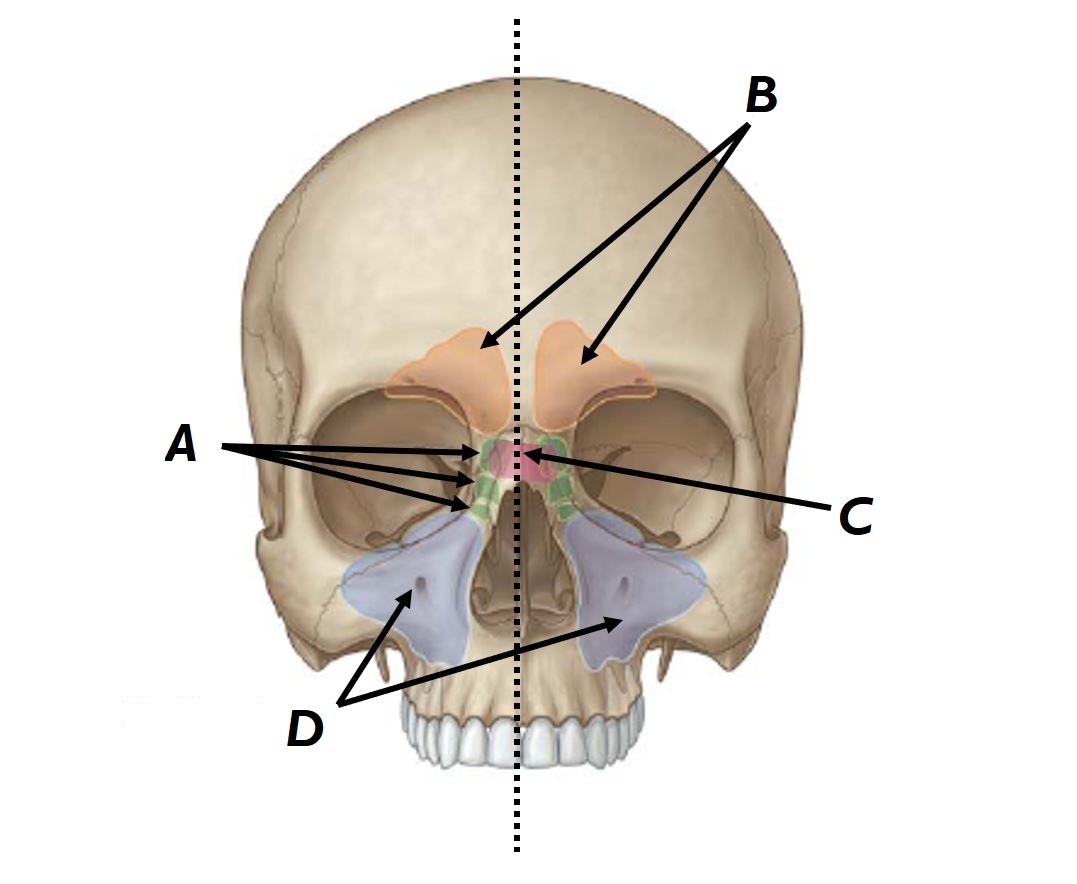

Name bones A to D

A - Right maxilla

B - Vomer

C - Ethmoid bone (perpendicular plate)

D - Frontal bone

Name bones A, B and C

A - Superior nasal concha

B - Middle nasal concha

C - Inferior nasal concha

Name structures A to D

A - Ethmoid air cells

B - Frontal sinuses

C - Sphenoid sinuses

D - Maxillary sinuses